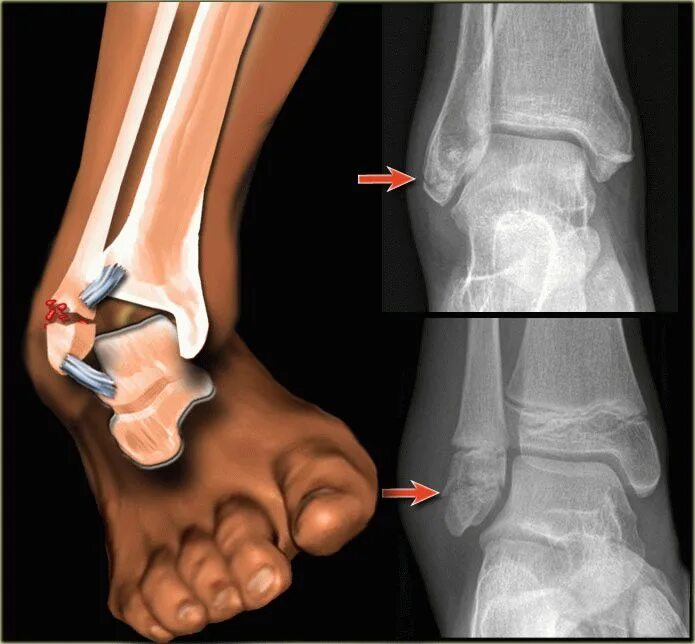

Что делать чтобы перелом быстрее сросся